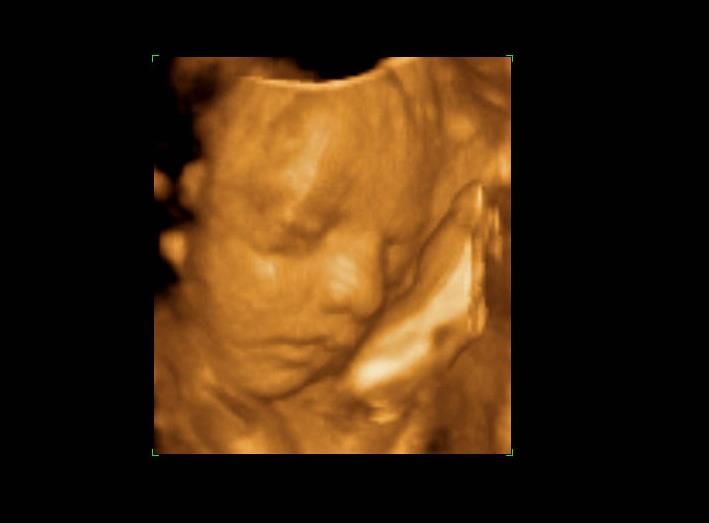

Based in Westfield, New Jersey, Belly 2 Birth Imaging lets expectant moms and dads see their baby for the first time even before the due date. Providing comprehensive 3D and 4D ultrasound in NJ, the company is all about ensuring that parents see their baby - every yawn and smile, or that precious moment of the little one sucking a thumb.

Explaining the technology behind pregnancy ultrasounds, Belly2BirthImaging.com notes that its leading 3D ultrasound in Westfield, NJ allows parents to spend intimate moments with their baby and see the miracle of life taking place first hand. While a 3D ultrasound is a still image, 4D adds the dimension of motion to that image - allowing it to more clearly capture and help identify the little bundle's unique physical traits and even personality characteristics.